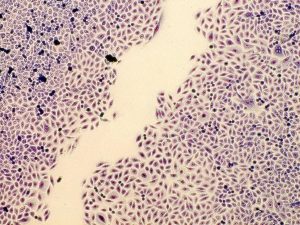

Zur Untersuchung der Zellvitalität verwendete das Institut Bindegewebszellen. Bei diesem Test wird die Zellaktivität über eine Farbreaktion getestet: Je höher die Zellvitalität, desto intensiver wird die Farbe der Reaktionslösung und diese Intensität lässt sich photometrisch bestimmen. Auch bei diesem Test zeigte sich, dass die beiden Quellwässer die Zellaktivität in „einer dosisabhängigen Weise statistisch signifikant stimulieren“. Das handelsübliche stille Wasser bewirkte hingegen eine „statistisch signifikante Reduktion der Zellvitalität“, abhängig von der Dosis. Eine Verbesserung der Zellvitalität ist in der Regel mit einer Förderung der Zellregeneration gekoppelt. Um dies zu testen, wurden Bindegewebszellen in strikt voneinander getrennten Bereichen aufgebracht, so dass definierte zellfreie Bereiche entstanden. In diese zellfreien Bereiche konnten die Zellen einwandern und dort durch verstärkte Zellteilung den zellfreien Bereich wieder schließen. Für jede Testkonzentration von Wasser nahm das Institut 18 Messungen in dreifachen unabhängigen Versuchsansätzen vor. Schnell zeigten sich „erhebliche Unterschiede“ zwischen den Wässern. Während es unter dem Einfluss der Quellwässer innerhalb von 24 Stunden zu einer mehr oder weniger vollständigen Neubesiedlung der zellfreien Zone kam, bewirkte das stille Testwasser nur eine unwesentliche Veränderung der Zellregeneration. Besonders die St. Georgsquelle war hier herausragend und zeigte schon bei einer Dosis von zehn Prozent des Wasservolumens „eine signifikante Stimulation im Vergleich zur Kontrolle“. Mit steigender Dosis zeigte aber auch die St. Leonhardsquelle eine vergleichbare Wirkeffizienz.

Mikrofoto vom Kontrollbild ohne Testwasser, die zellfreie Zone in der Mitte wird innerhalb von 24 Stunden nicht vollständig neu besiedelt